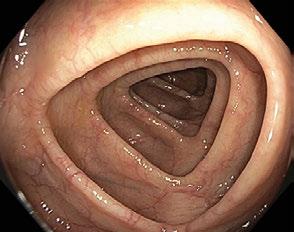

Obr. 1.4 Sigmoideum s kruhovým až oválným lumen

bývá díky dobře vytvořenému peritoneálnímu závěsu (mesocolon sigmoideum) mobilní a v typickém případě má díky dvěma ohbím tvar řeckého písmena ζ (sigma) nebo názorněji písmene N. Peritoneální adheze v oblasti pánve (nejčastěji v důsledku chirurgických intervencí, radioterapie, zánětlivých afekcí, endometriózy atd.) mohou pevně fixovat jinak mobilní angulace sigmoidea (obr. 1.4).